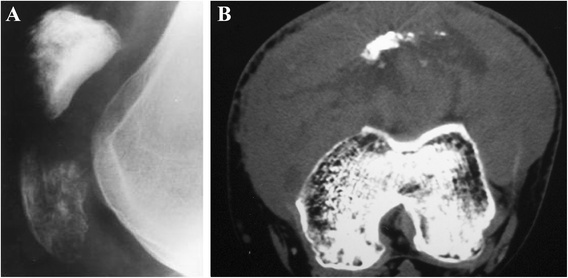

The patella is an uncommon location for cancerous occurrence and development. The majority of tumors of the patella are benign, with a significant incidence of giant cell tumors and chondroblastoma. With the development of modern diagnostic technologies, there appear however many other histological types which raise challenges of diagnosis and treatment. In this article, we review the reported histological types of primary patellar tumors. Specifically, epidemiology, symptomatology, imageology, histopathology, and treatment options for these histological lesions will be discussed, respectively. As there is an increasing focus on the diagnosis and the treatment of these lesions, the availability of the integrated information about primary patellar tumors becomes more significant.